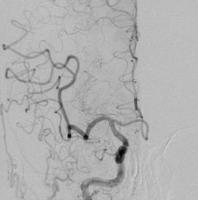

脳動脈瘤塞栓術

脳動脈瘤が破裂して出血するのを防ぐために、脳動脈瘤にコイルを詰めて血液が入り込まないようにする手術です。

術後に血管撮影を行うと、コイルで置き換わった脳動脈瘤は造影剤が入らないため描出されなくなります。